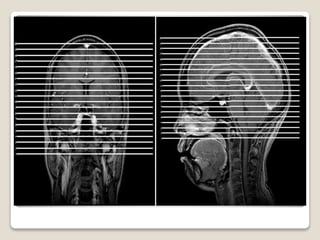

RM OBSTÉTRICA